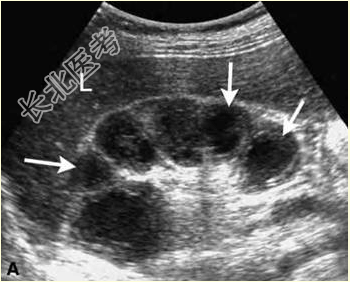

- [材料题] 患者男,40岁,因“尿频、尿急、尿痛及血尿3个月”来诊。尿常规:大量白细胞和少量红细胞。声像图表现见下图。

- 多项选择题1.其超声诊断包括

A、肾积水

B、肾内钙化灶

C、肾感染性病变

D、肾结核

E、多囊肾

F、肾囊肿